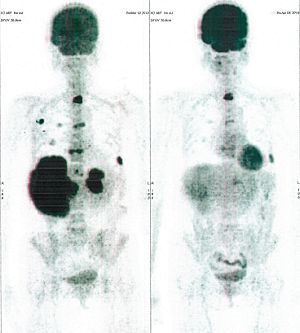

CASE NO: 1 - A FEW MONTHS LATER

A few months after successful treatment for hepatocellular carcinoma, and partially successful for stomach cancer, the PET/CT scan showed the stomach cancer becoming very active, with several metastases to the parts of the liver not previously involved by hepatocellular carcinoma. After a few treatment, all the active stomach cancer lesions in the stomach and in the liver went into remission.

CASE NO: 2 (HEPATOCELLULAR CARCINOMA)

A 40+ man with hepatocellular carcinoma, an incurable cancer. After 2 treatment, the activity of the hepatocellular carcinoma is less.

CASE NO: 2 (HEPATOCELLULAR CARCINOMA) - After a few more treatments

After another few treatment, the activity of the hepatocellular carcinoma is much less. The patient never came back for further treatment, but this case, and case no: 1, shows that incurable hepatocellular carcinoma, often seen in hepatitis B and C patients, can be cured.